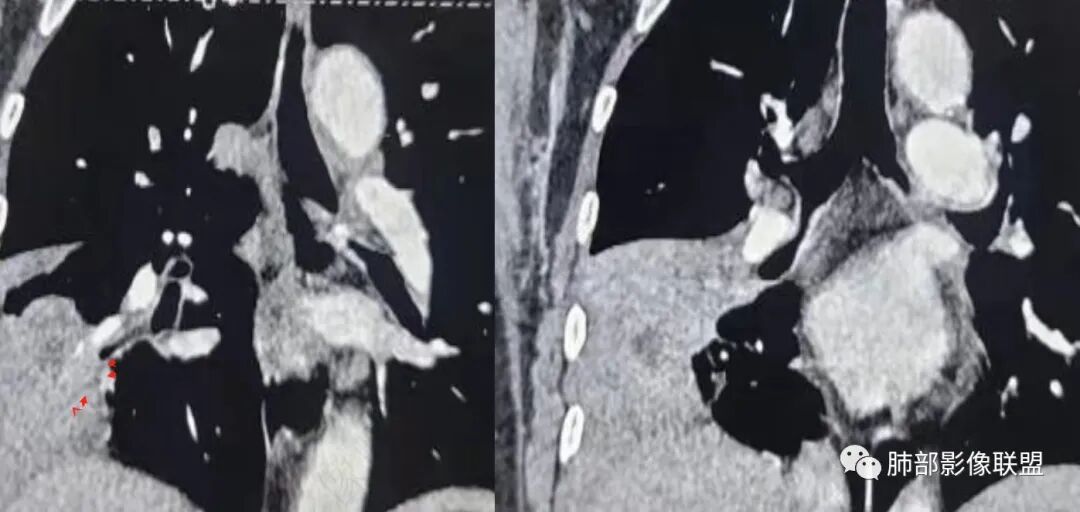

这个病例,看长轴、形态,首先跨叶,里面的坏死腔,它是相通的,就是跨中叶及前基底段。

然后中叶与下叶的坏死腔病灶是相通的,病灶是跨叶的,胸膜糊墙为主。

我要看一下下叶。还想重建一下,就是按照我自己理解的长轴去重建出这个病灶的整体形态,我当时一看,好像侧向融合的病灶。侧向融合的病灶考虑慢性炎性病变的,有几种,这样大片的病灶,常规都考虑特殊感染多一些,比如隐球,放线菌,奴卡等,都可以这样的改变。

现有的CT,里面存在坏死腔。炎症肯定有,是否同时合并肿瘤的问题?我需要详细的图将内部结构逐步剖析出来,看看能否有新的依据

南边:跨叶、楔形/边缘平直、支气管壁无破坏/连续/局部无膨大、实变区肺动脉走形自然、实性部分均匀、延迟强化、坏死腔内壁光滑/内壁强化环/近端与支气管相通,这些点均支持炎性。所以综合分析:符合炎性。